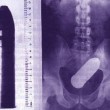

Tutte queste persone sono state ricoverate con diversi oggetti incastrati nell’ano e non solo: dal cellulare alle chiavi di casa, passando per proiettili e giocattoli come macchinine e pupazzetti.

Anche il sex toy, a quanto pare deve essere usato responsabilmente. Specialmente quando l’oggetto è improvvisato. E chi rimane con l’oggetto incastrato cosa deve fare? Come spiegano i medici dei pronto soccorso, non bisogna provare a risolvere il problema da soli senza andare in ospedale. In molti casi infatti, alcune persone vengono ricoverate sia con l’oggetto, sia con le pinze utilizzate per recuperare l’oggetto, conficcate nell’ano.